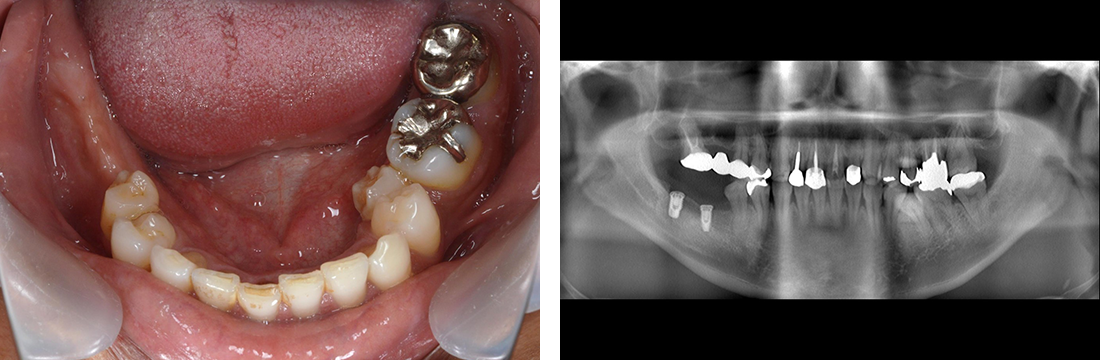

インプラント症例 Case3

Treatment cases

Before

After